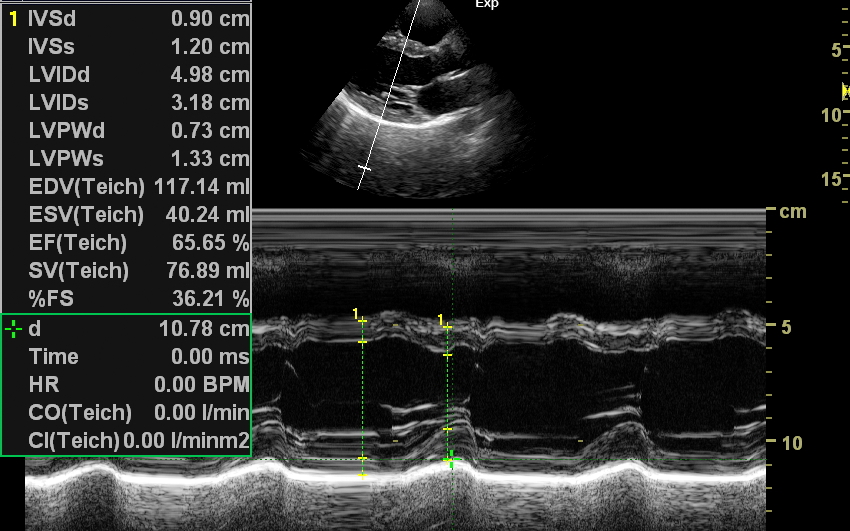

Badanie echokardiograficzne, nazywane także echo serca lub USG serca jest jedną z podstawowych metod diagnostyki kardiologicznej. W badaniu tym ocenia się zarówno morfologię narządu, jak i jego funkcję w postaci pomiarów wielkości jam serca, grubości mięśnia sercowego, czynności skurczowej oraz rozkurczowej lewej i prawej komory, oceny funkcji zastawek serca, wyglądu wsierdzia, osierdzia, a także w postaci pomiarów aorty, poszukiwania obecności patologicznych objawów sercowych związanych z chorobami innych narządów (np. choroby płuc, nadciśnienie tętnicze).